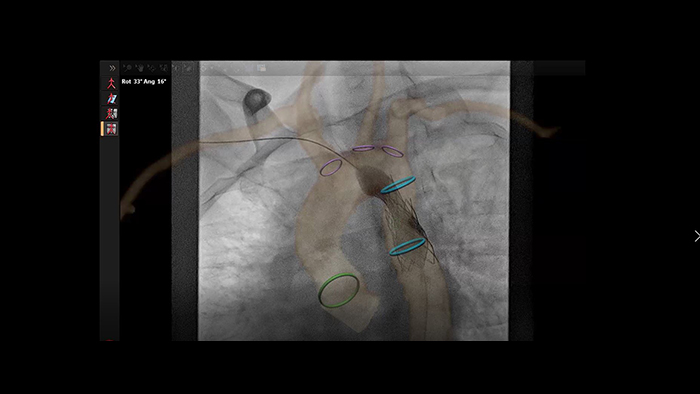

Guía de colocación de stent en coartación aórtica con VesselNavigator

Análisis automático de vasos de angiografía rotacional con SmartCT

Guía en tiempo real de SmartCT